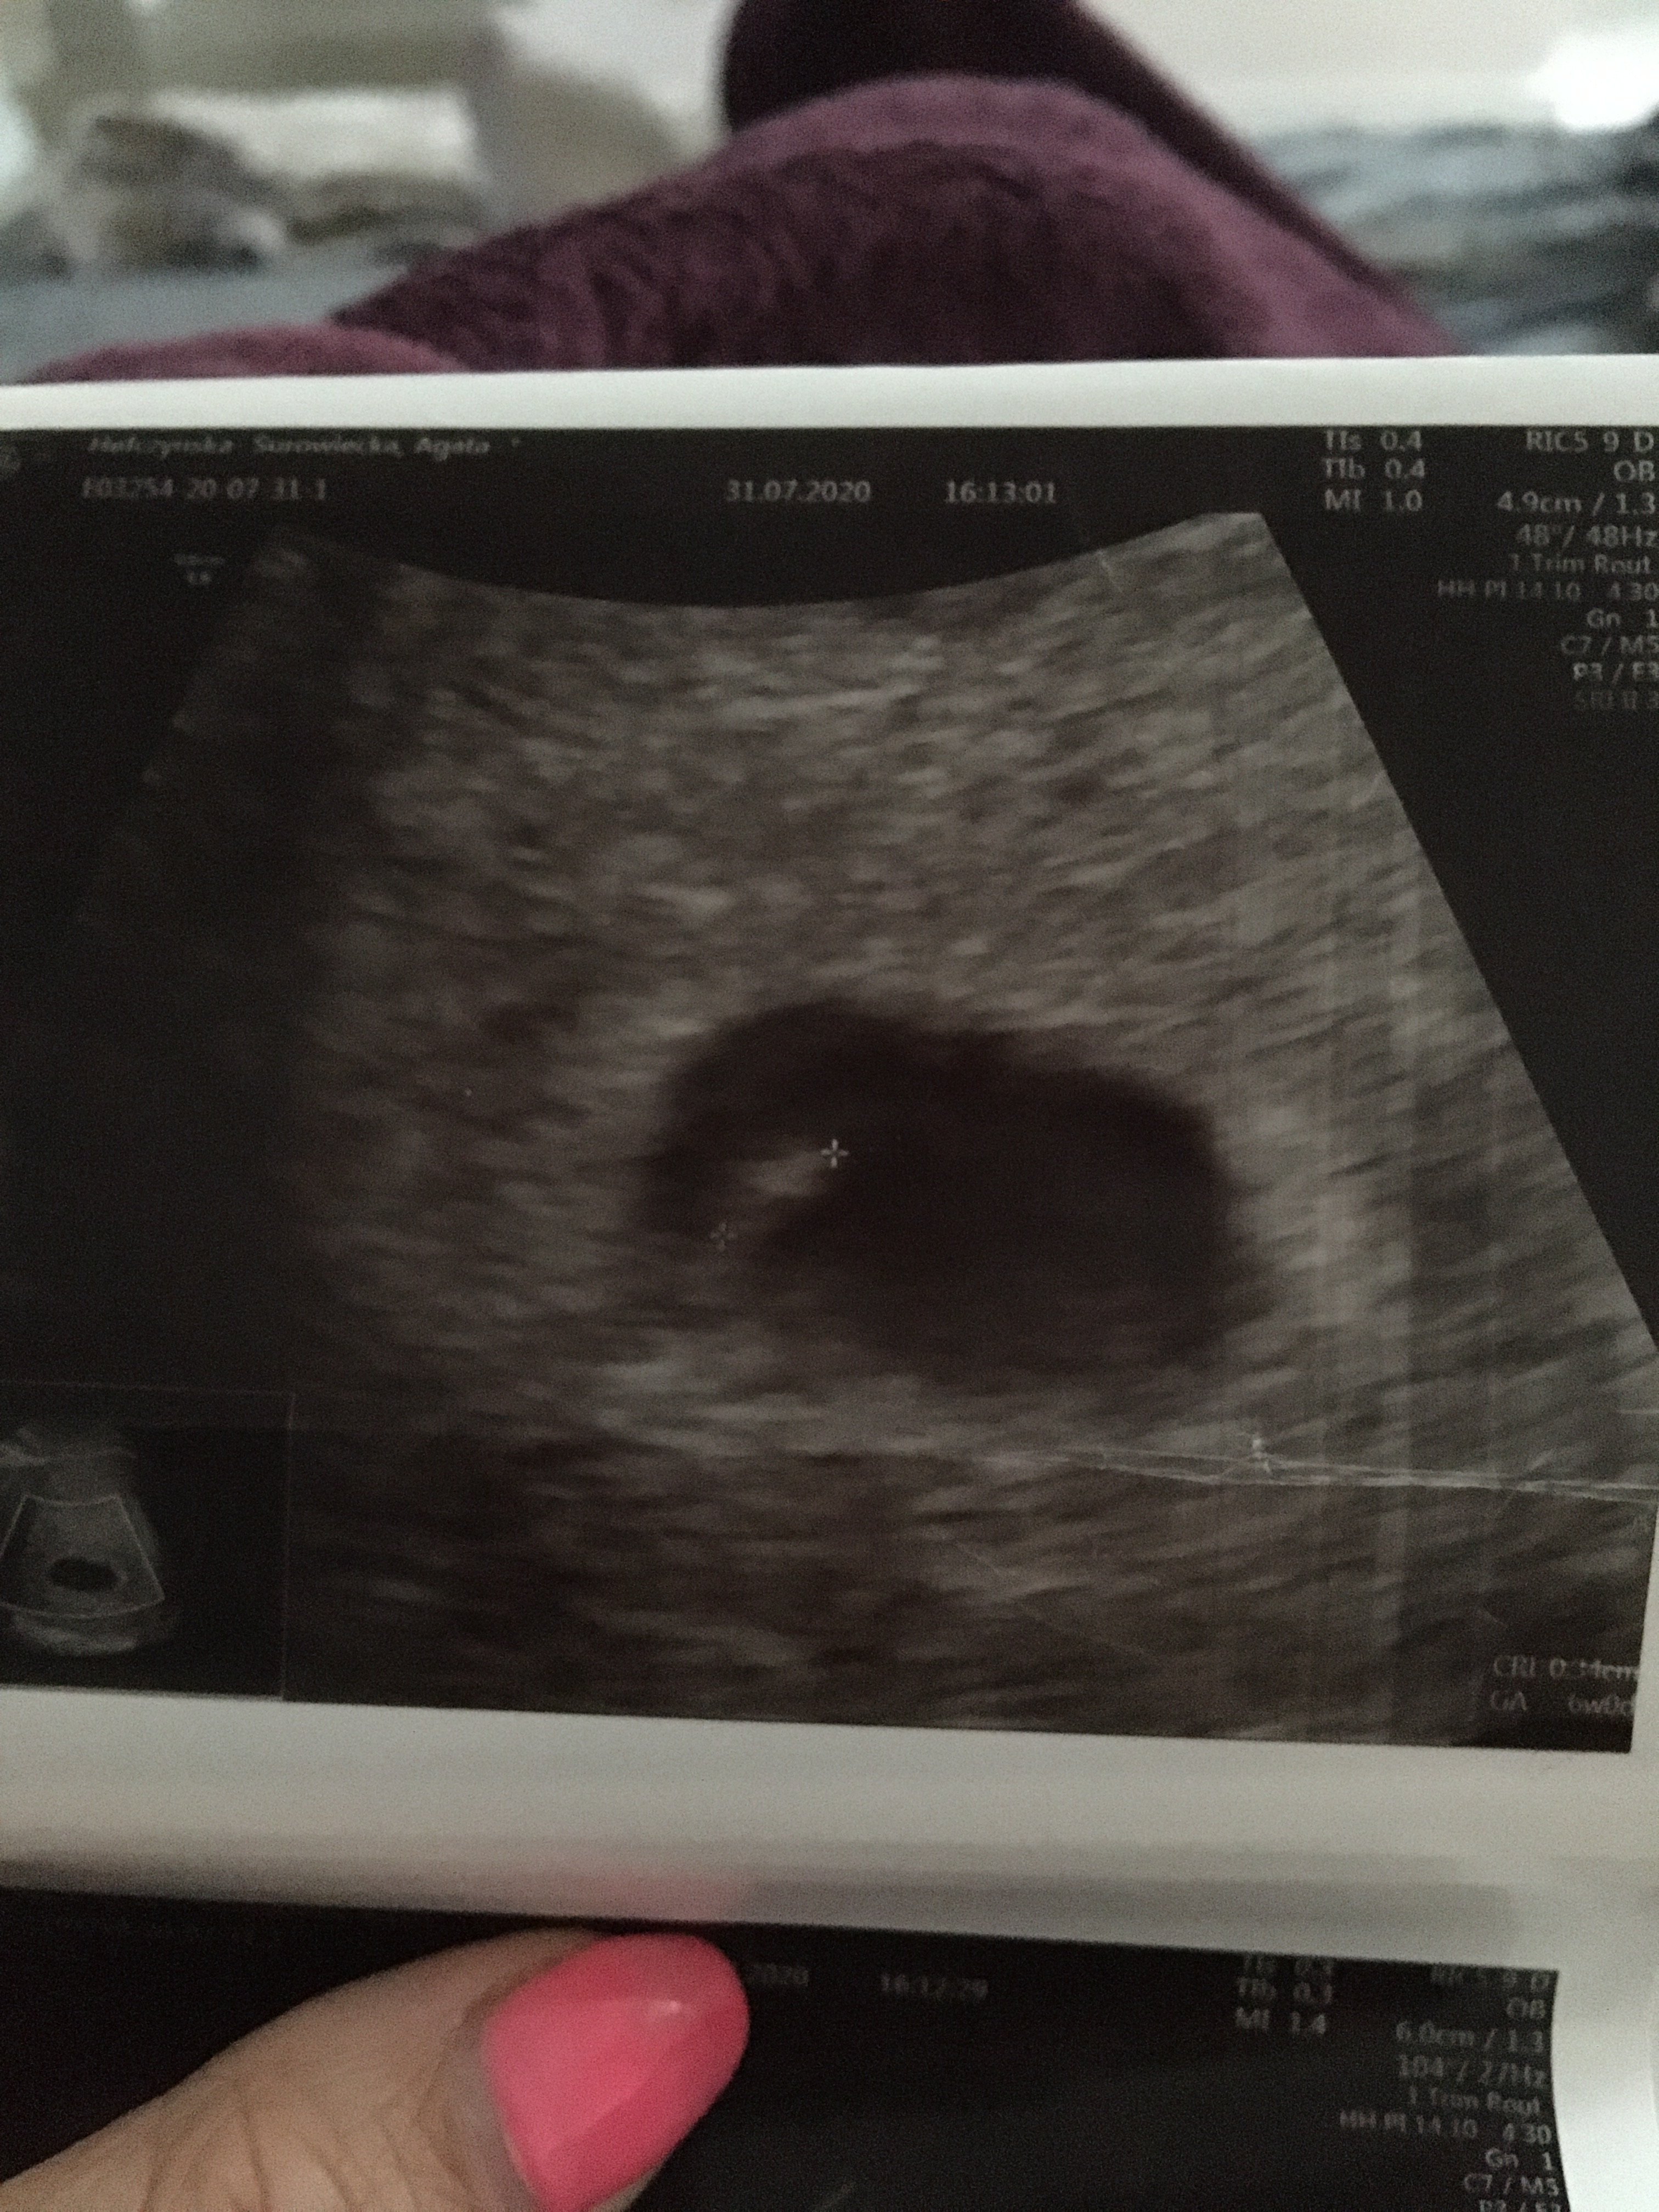

Serduszka chyba nie było tzn lekarz był bardzo oschły i nie dawał dojść do słowa, tak wyglada usg 6,1 dzień. Czy uważacie ze to nie jest dziwne ze jest tylko taki pęcherzyk ?

• image.jpg

image.jpg

1,8 MB · Wyświetleń: 6 708